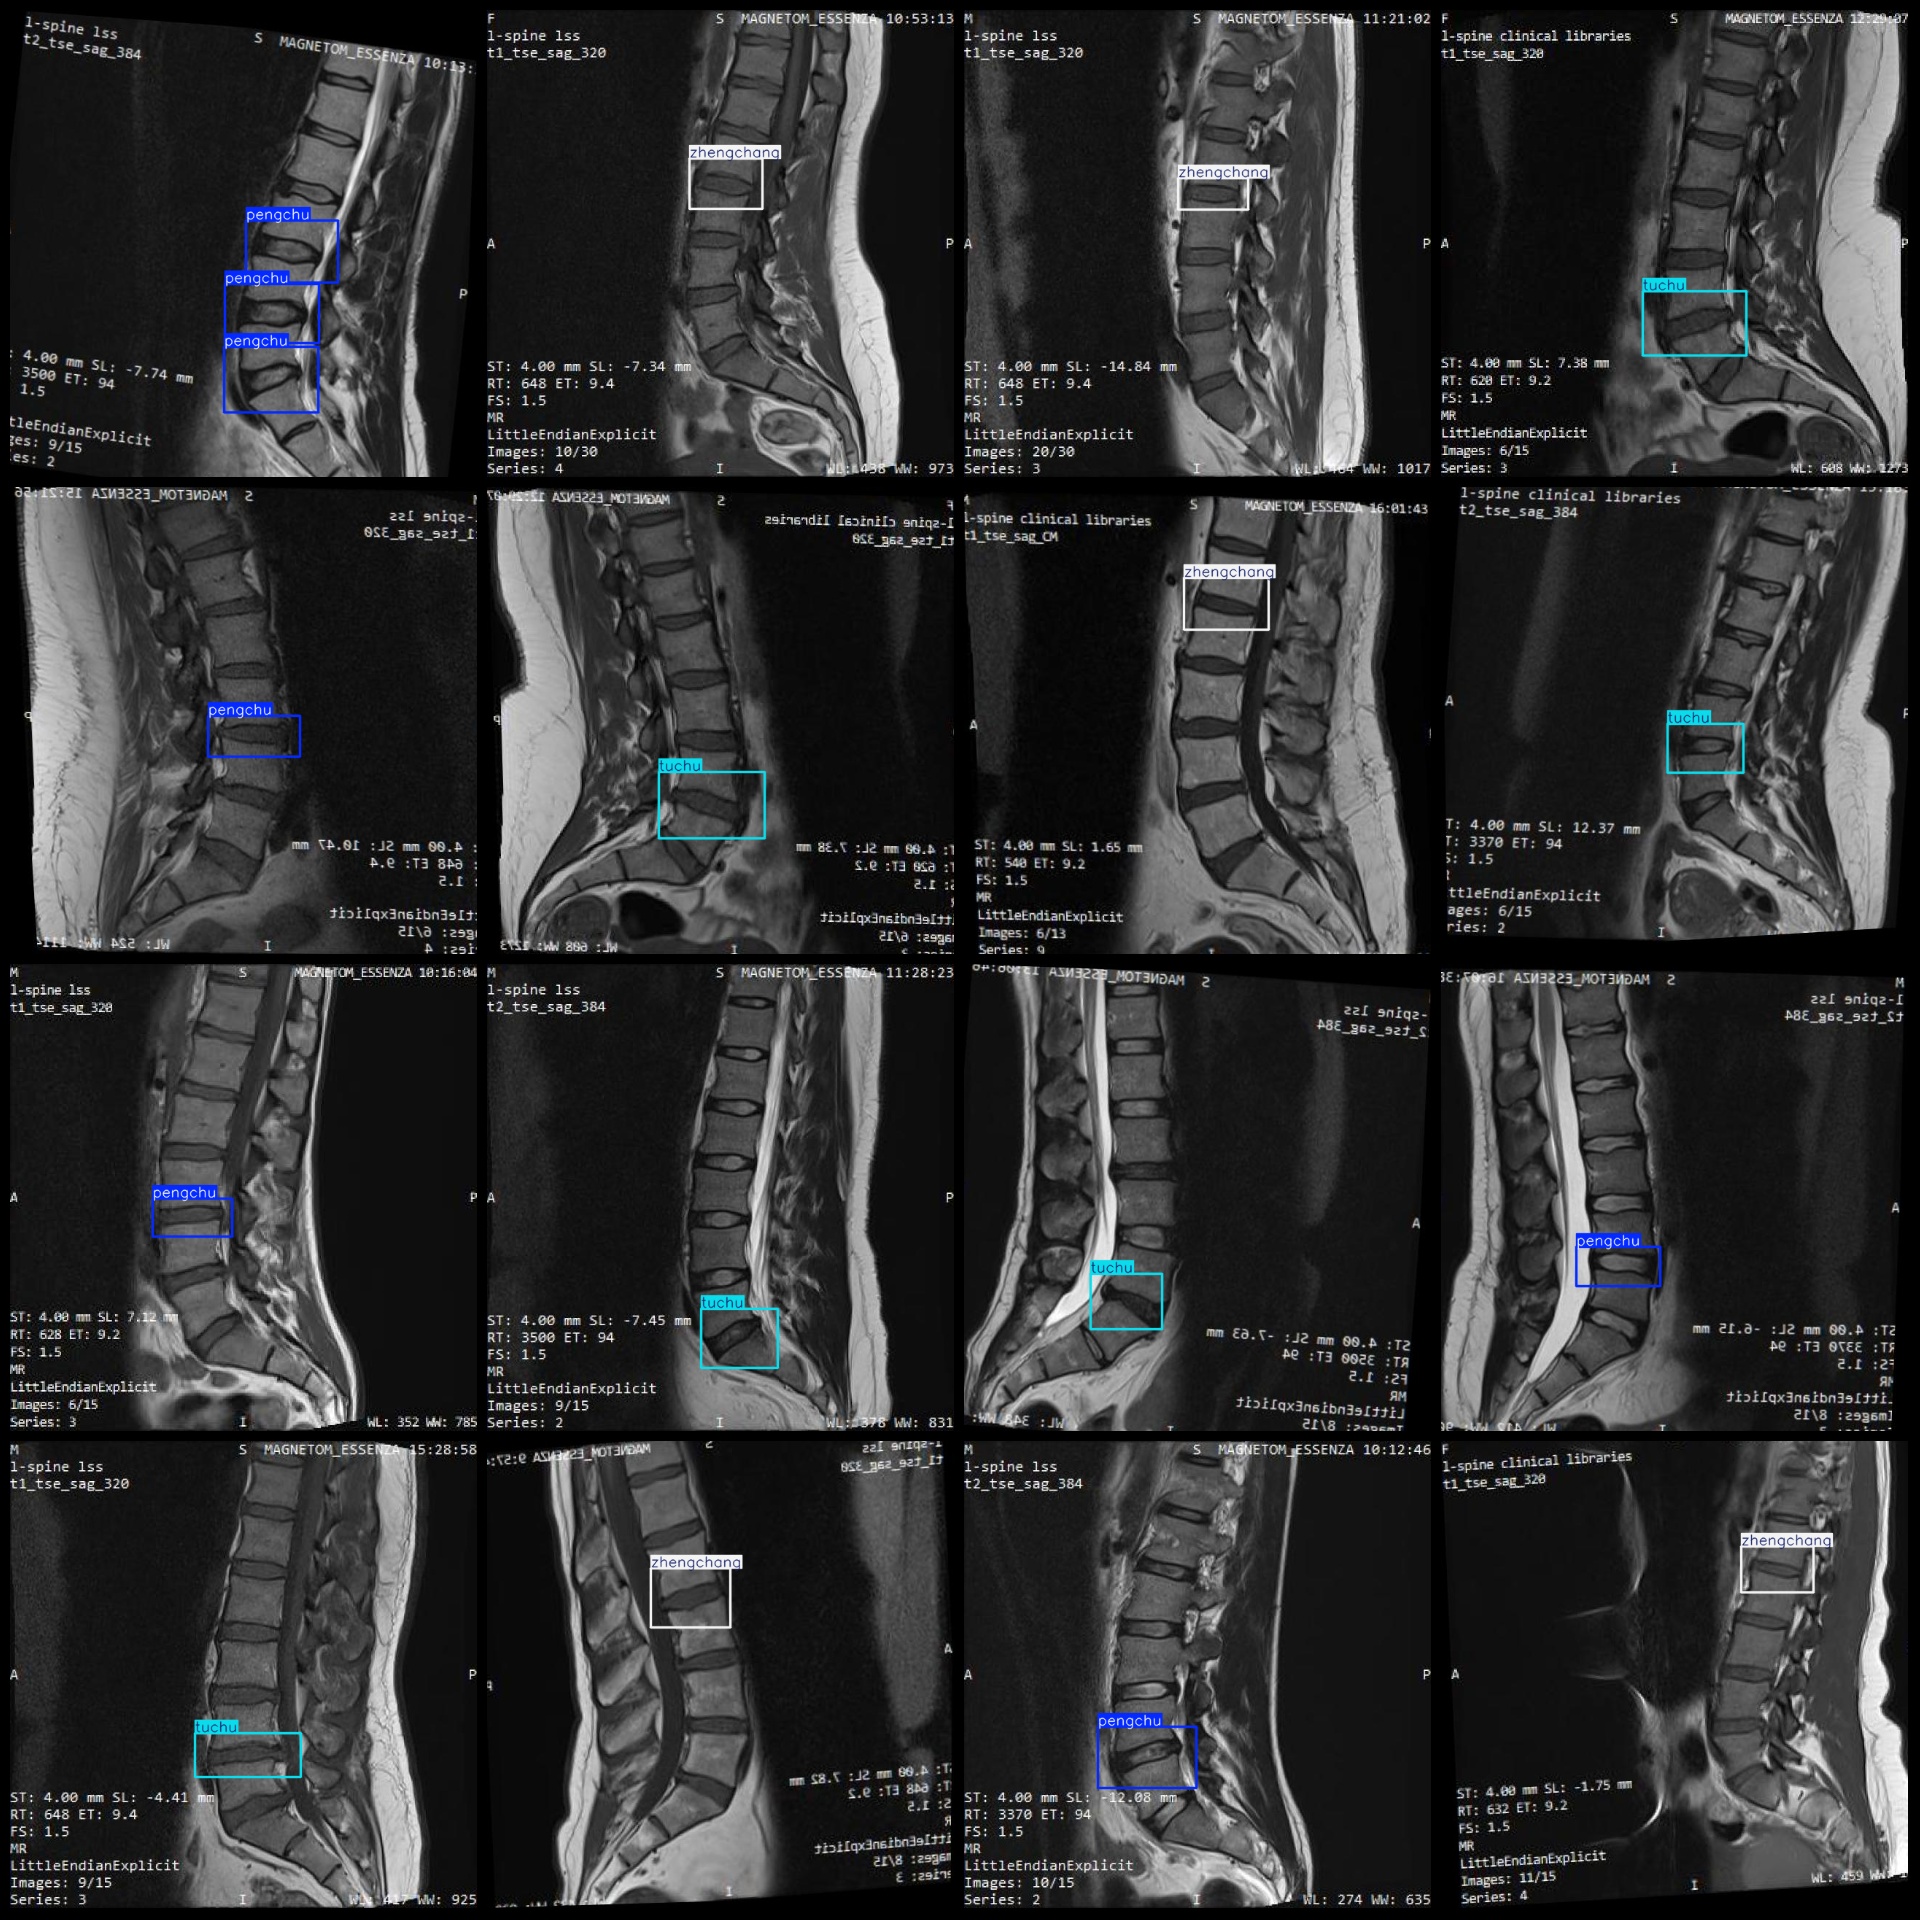

标注例子:

标注类别名称(注意yolo格式类别顺序不和这个对应,而以labels文件夹classes.txt为准):["pengchu","tuchu","zhengchang"]

pengchu(膨出) 框数 = 274

tuchu(突出) 框数 = 266

zhengchang(正常) 框数 = 282